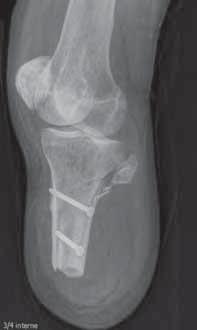

3.Wskazanianowotworowe

3.1. Wskazania urazowe , acute renal failure

dalszej podudzia